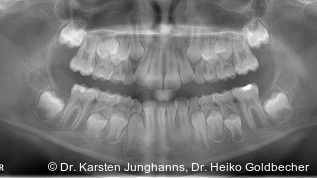

Dieser Beitrag soll zum einen dem Leser einen Überblick über aktuell erhältliche Systeme im Bereich Modell- und Abdruckscanner (Abb. 3), CBCT-Scanner sowie intraorale Scanner (Abb. 4a, b) geben und zum anderen als eine Art Wegweiser in die digitale Welt fungieren. Anhand der angefertigten Tabellen (siehe Tabellen 1 bis 3) lassen sich direkte Vergleiche zwischen den einzelnen Systemen innerhalb der Kategorien anstellen. Mit dem Fokus auf den praxisgerechten und betriebswirtschaftlichen Einsatz in der alltäglichen kieferorthopädischen Praxis soll dem Leser vor allem nahegelegt werden, „was zu beachten ist“, wenn man eine Anschaffung ernsthaft in Erwägung zieht. In diesem Zusammenhang werden dem Interessierten auch Alternativen zu teuren und risikobehafteten Investitionen aufgezeigt. Bevor man sich auf die momentan erhältliche Produktvielfalt im Bereich „digitale Kieferorthopädie“ stürzt und sich von diversen Firmen oder Depots verleiten lässt, sollte zunächst Klarheit hinsichtlich der eigenen Bedürfnisse für die Praxis bestehen. Dabei ist der Aspekt, ob es nun ein Modell- und Abdruckscanner, ein CBCT-Scanner oder ein intraoraler Scanner werden soll, vorerst zweitrangig zu betrachten. Lediglich bei dem Vorhaben, eine abdrucklose kieferorthopädische Praxis anzustreben, scheint die Anschaffung eines intraoralen Scanners alternativlos. Da jedoch viele unserer alltäglichen Abläufe in der Kieferorthopädie weiterhin Modelle bedürfen, ist der Kauf eines intraoralen Scanners oftmals mit der Notwendigkeit eines 3-D-Druckers behaftet. Die Schaffung einer abdrucklosen Praxis sollte somit nicht als alleiniges Entscheidungskriterium bei einem Erwerb eines Scanners dienen. Das Spektrum der Möglichkeiten nach Erfassung der Oberfläche lässt sich momentan auf zwei Kernbereiche konzentrieren und hängt in den meisten Fällen vom Umfang der Software ab. Hierbei spielen neben der simplen Digitalisierung von Modellen vor allem die Möglichkeit der Modellanalyse und Erstellung von Behandlungsplanungen eine entscheidende Rolle. Die Herstellung von kieferorthopädischen Arbeitsmodellen und Geräten anhand eines Datensatzes sowie die Anfertigung von zahnärztlichen Schienen/Table-Tops bei CMD-Patienten unter Nutzung eines virtuellen volladjustierten Artikulators, scheint ebenfalls in greifbarer Nähe zu sein und sollte unbedingt bei einer prospektiven Kaufentscheidung eine Rolle spielen.

Im Hinblick auf markterhältliche CBCT-Scanner gibt es momentan nur ein System der Firma Planmeca® (ProMax 3D®). Anders als bei den herkömmlichen Geräten müssen hier die erhobenen DICOM-Daten erst in STL-Daten konvertiert werden, um schließlich digitale Modelle zu erhalten. Ebenso fällt die Auflösung bei den röntgenerhobenen digitalen Modellen erheblich niedriger aus und sollte aus diesem Grund nur für Dokumentationszwecke herangezogen werden. Als vorteilhaft kann die integrierte Scanfunktion ohne zusätzliche Investitionskosten gesehen werden.